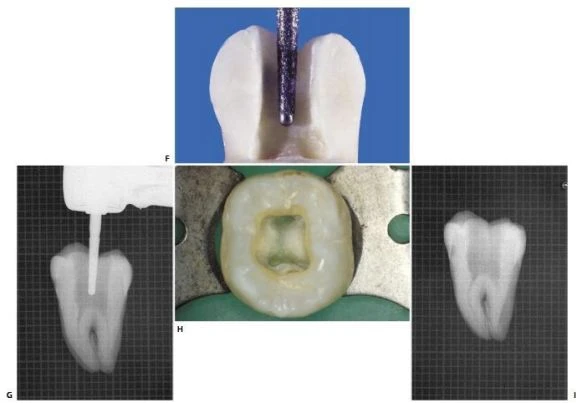

Hình 11.112. Trong một số trường hợp khác, ống tủy gần giữa được thấy ở 1/3 chóp của chân gần.

Hình 11.113. Điều trị lại R46 vì điều trị sót 2 ống tủy: ống xa ngoài và ống gần giữa. A. Phim trước điều trị. B. Xoang tủy sau khi bộc lộ 4 ống tủy. Chú ý sự hiện diện của 1 chỗ lõm ở vùng eo giữa 2 chân gần. C. Một file số 10 đi vào chỗ lõm và  rất dễ dàng đi vào ống tủy gần giữa, ống này có một lỗ chóp riêng. D. Xoang tủy sau khi sửa soạn 5 ống tủy E. Ba file chỉ ra rằng có 3 ống tủy riêng biệt ở chân gần  F. Phim sau điều trị. G. Một góc chụp khác cho thấy hình ảnh 5 ống tủy. H. 7 năm sau điều trị, tổn thương lành hoàn toàn.

Thương tổn trước đây không phải do vật liệu trám ra ngoài mà vì vi khuẩn còn lại trong ống tủy bị bỏ sót.